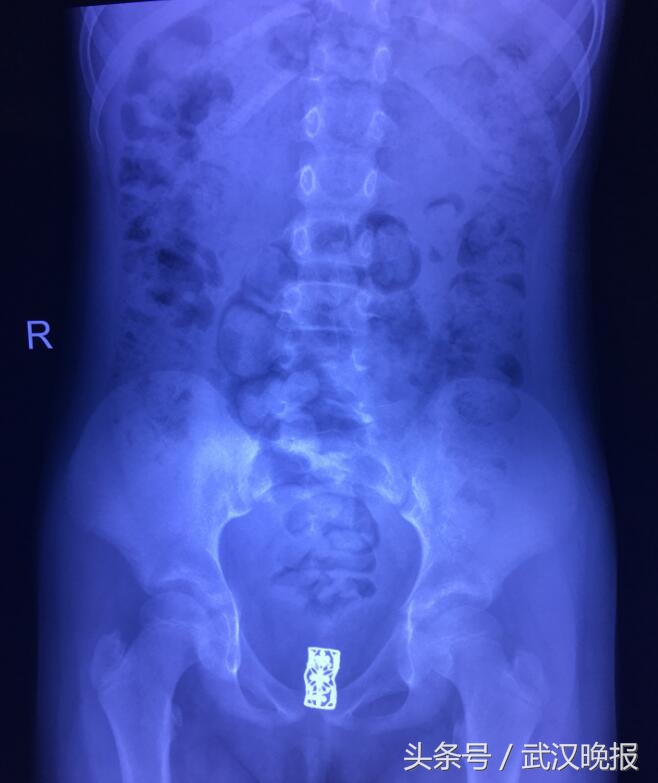

趁着爸爸回老家,昨天一家人赶到武汉儿童医院。泌尿外科主任李爽给楠楠做了检查,她从爸爸的描述中判断,楠楠体内很可能藏着异物。随后的检查证实了她的推断,X光片上清楚地看到在阴道附近有一个镂空花纹的长方形金属异物。

必须尽快手术取出!昨天一早楠楠就被推进了手术室。手术医生李刚告诉记者,楠楠*体下**灌满了脓性分泌物,周围全是湿疹和破溃,处女膜有陈旧性撕裂伤。膀胱镜在距离阴道口6厘米的地方找到了异物,已经被肉芽层层包裹,剥离后取出一个黑色的金属小发卡。他表示,不排除是他人将发卡塞入孩子体内,也可能是孩子好奇将异物塞入所致。经过几天的消炎治疗,楠楠就可以出院了。